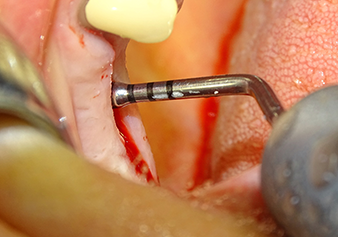

Preparazione e accrescimento della sede dell'impianto

Dopo un controllo intermedio (Fig. 4) è stata eseguita un'ulteriore fase di preparazione (Fig. 5). Lo strumento idraulico Z35P è stato utilizzato in un secondo momento per sollevare la membrana sino alla posizione desiderata (Fig. 6 e 7). In seguito alla suddetta operazione, si è proceduto ad una ulteriore preparazione piezochirurgica della sede dell'impianto conclusasi con l'applicazione della fresa e della fresa a spallamento sul diametro dell'impianto di 4,8 mm. Il materiale di rinforzo (dimensione delle particelle di ca. 0,8 - 1,6 mm) è stato introdotto sotto la membrana di Schneider prima che venisse inserito l'impianto (Fig. 8).

La sede dell'impianto viene estesa di 3,0 mm impiegando lo strumento I3A

Fig.5: nella fase successiva, la sede dell'impianto viene estesa di 3,0 mm impiegando lo strumento I3A (potenza 100%, fluido di raffreddamento 80%). Gli indicatori di profondità evitano in modo affidabile una preparazione eccessivamente profonda.

La membrana di Schneider viene allungata di 1,5-2 mm sopra l'accesso del tessuto osseo

Fig.4: Controllo intermedio: l'altezza ossea sopra il seno mascellare è di ca. 4 mm palatale e buccale; la membrana di Schneider viene allungata di 1,5-2 mm sopra l'accesso del tessuto osseo.